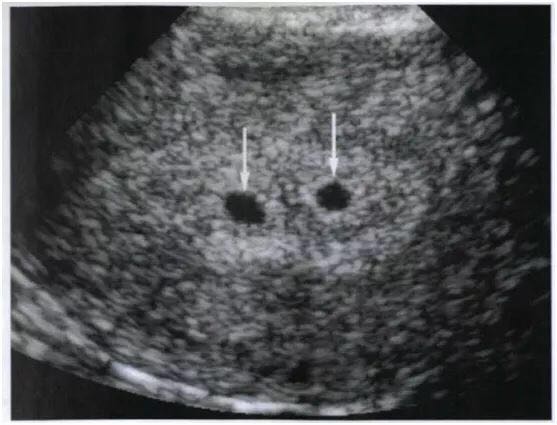

图片说明:孕早期B超提示两个孕囊。图片来源于@上海新华医院孕婴保健。 3问:B超说是双胎,还要加做其他检查吗? 答:一般,双胎依赖超声诊断。 另一个辅助检查方法是MRI。但不作为双胎常规的诊断方法,仅在胎儿有异常时选用。 临床查体也能发现双胎表现,比如腹部四步诊可以发现子宫异常增大;多个肢体和胎头;不同部位听到的两个不同胎心。 以往曾有X线检查诊断方法。但考虑到射线对胎儿的影响,已经全面取消。 4问:双胞胎有没有可能误判? 答:在孕早期,可能出现将孕囊出血暗区误诊为妊娠囊。但随着妊娠孕周增加可鉴别。 孕中期,较不容易误诊。 孕晚期由于胎儿较大,空间有限,容易漏诊连体双胎。 但若一胎早期死亡吸收,可出现早期双胎、晚期单胎的现象。 5问:产后,检查胎盘、脐带,能证明单双胎? 答:双胎在分娩时完全能诊断。一是可以检查胎儿为两个。二是两个胎盘及各自连接的脐带,或一个胎盘有两根脐带,都是双胎表现。 6问:4维超声比3维,准吗? 答:“四维”的概念就是“三维”(长*宽*高组成的立体空间)+时间轴。因此,只要是可以做三维彩超的超声机,就能做四维(时间浸润在检查过程中)。即,在动态过程中,检查胎儿的器官、外表和活动的可能异常。